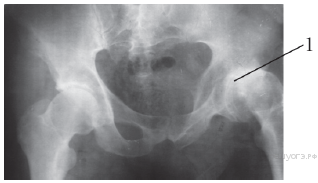

Какой сустав обозначен на рентгеновском снимке цифрой 1?

Варианты ответов

- тазобедренный

- голеностопный

- локтевой

- лучезапястный